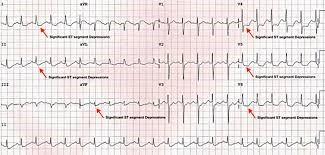

Evaluarea se bazează pe o combinație între anamneză clinică detaliată, examinare fizică și investigații paraclinice adecvate. Semne precum durere toracică de nouă apariţie, dispnee, greaţă sau simptome neurovegetative pot ridica suspiciunea de afectare ischemică; diagnosticul concret se conturează prin integrarea rezultatelor clinice cu examenele complementare.

R: Diagnosticul se bazează pe evaluarea clinică şi pe investigaţii medicale, care pot include electrocardiogramă, teste funcţionale sau imagistice cardiace şi analize de laborator. Alegerea testelor depinde de tabloul clinic şi este stabilită de medicul cardiolog.